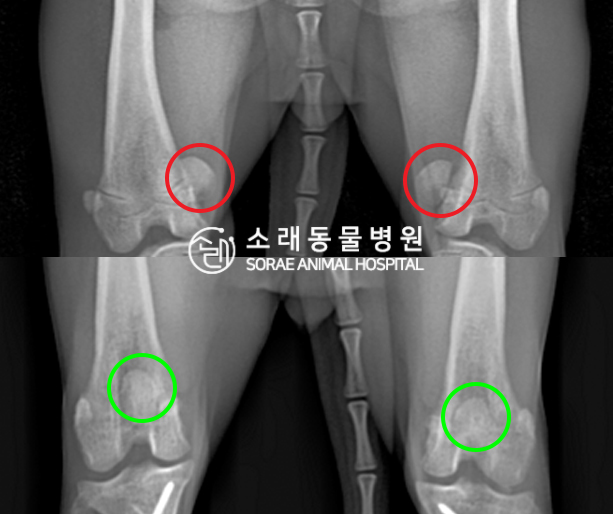

수술전과 수술후에 촬영한 쿠키의 슬개골

방사선 사진입니다. 나란히 놓고 비교해보니

슬개골의 위치에 확연한 차이가 있는 것을

확인해 볼 수 있는데요. 내측으로 탈구되어 있던

슬개골이 원래 제자리인 활차구에 예쁘게

자리 잡고 있는 모습을 확인할 수 있었습니다.